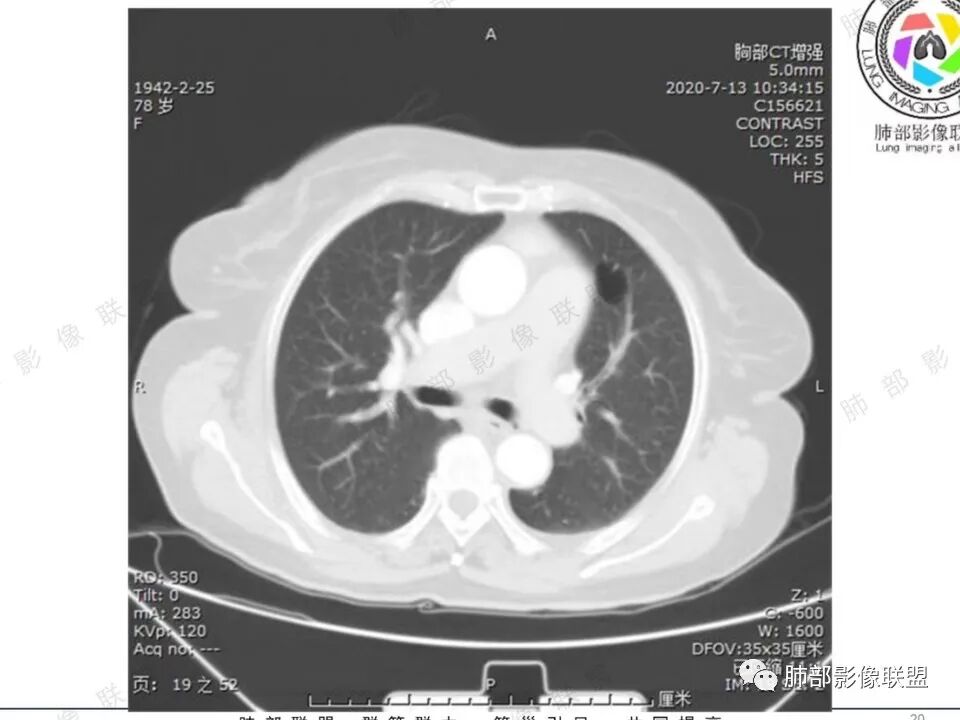

一切∮随缘:

左肺下叶空洞性病变,洞壁厚薄不均匀,洞壁似见小泡状低密度影,病变宽基底与与胸膜相连,周围伴有磨玻璃影,增强后可见壁强化,边界欠清,周围未见播散灶,左肺上叶纵隔胸膜下肺气囊,老年女性,主要是科室咳痰,咯血无发热,孤立性空洞性病变,考虑:腺癌(囊腔性肺癌),鉴别:隐球菌,放线菌,奴卡菌。

王开金江津中心医院呼吸科:老年女性,糖尿病,咳嗽,咳痰,痰血,无发热,血分析正常,左下叶背段空洞,周围光滑,内有洞丝,壁结节,无卫星灶,考虑肺癌,鉴别结核。

穿越七海的风:老年女性,糖尿病,咳血,左肺下叶空洞性病变,壁薄光滑,空洞内丝状物,壁结节无强化,周围有晕,考虑真菌感染毛霉?鉴别肺腺癌。

丽:老年女性,左肺下叶胸膜下空洞性病变,薄壁,边缘模糊有晕,空洞内不干净,丝丝缕缕,增强后洞壁有强化,有糖尿病病史,考虑感染性病变,毛霉?曲霉?

大雄:左下叶孤立空洞,病灶整体较僵硬,壁厚薄不均,无明显卫星灶,局部强化,倾向囊腔型肺癌。

徐飞:老年女性,咳血,糖尿病,左肺下叶囊腔性病变,内见少许分隔,增强后见部分壁不规则增厚及轻中度强化,纵隔多发肿大淋巴结,考虑囊腔型腺癌,鉴别毛霉菌感染。

必有路:肿瘤指标阴,胃肠道的转移基本不考虑,周围实际上比较干净,感染类的,不符   老年人   毛霉菌往往要有酮症基础,所以,囊腔肺癌>真菌(毛霉)